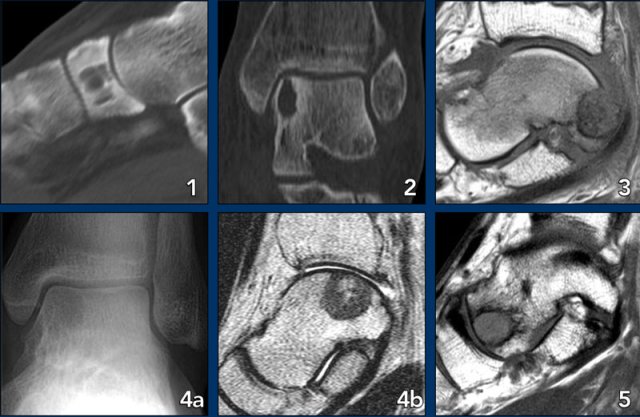

Foot lesions

Here some typical examples of bone tumors in the foot:

- Geode or subchondral cyst in the navicular bone

- Geode or subchondral cyst in the tarsal bone

- Chondroblastoma in the tarsal bone

- X-ray and MRI of a chondroblastoma in the tarsal bone

- Aneurysmal bone cyst in the tarsal bone

- Chondromyxoid fibroma (CMF) in the calcaneus

- Same patient MRI

- CMF in the second metatarsal bone

- Ewing sarcoma in the calcaneus

- Glomus tumor